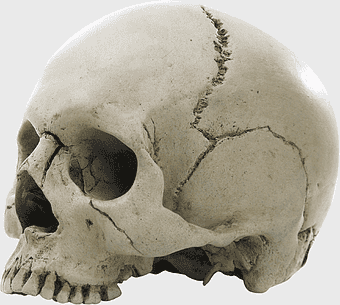

fibrous joint skull, human anatomy bone structure, temporomandibular joint, connective tissue in skull, cranial sutures, skeletal head anatomy, skull joint analysis -